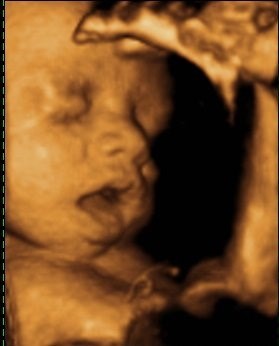

Søger man på Google kommer der kun 3D-billeder.

Så jeg vil høre om nogen herinde har et billede eller to fra uge 28 de vil vise? Og hvor lang var jeres baby, og fik I vægt at vide?